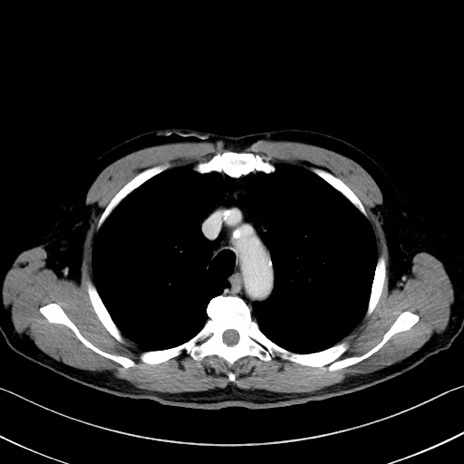

症例35(横断像)

【症例】70歳代 男性

【主訴】腹部膨満、嘔吐

【現病歴】昨日より腹部膨満感出現。本日増悪し、仙痛出現。嘔吐あり、受診。

【既往歴】糖尿病、胆摘後

【身体所見】BP 149/80mmHg、HR 74/min、BT 35.9℃、腹部:膨満、軟、圧痛なし。腸雑音減弱あり。上腹部正中切開瘢痕あり。

【データ】WBC 13500、CRP 1.72